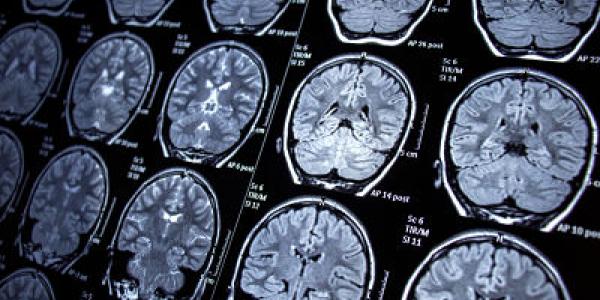

lesiones cerebrales